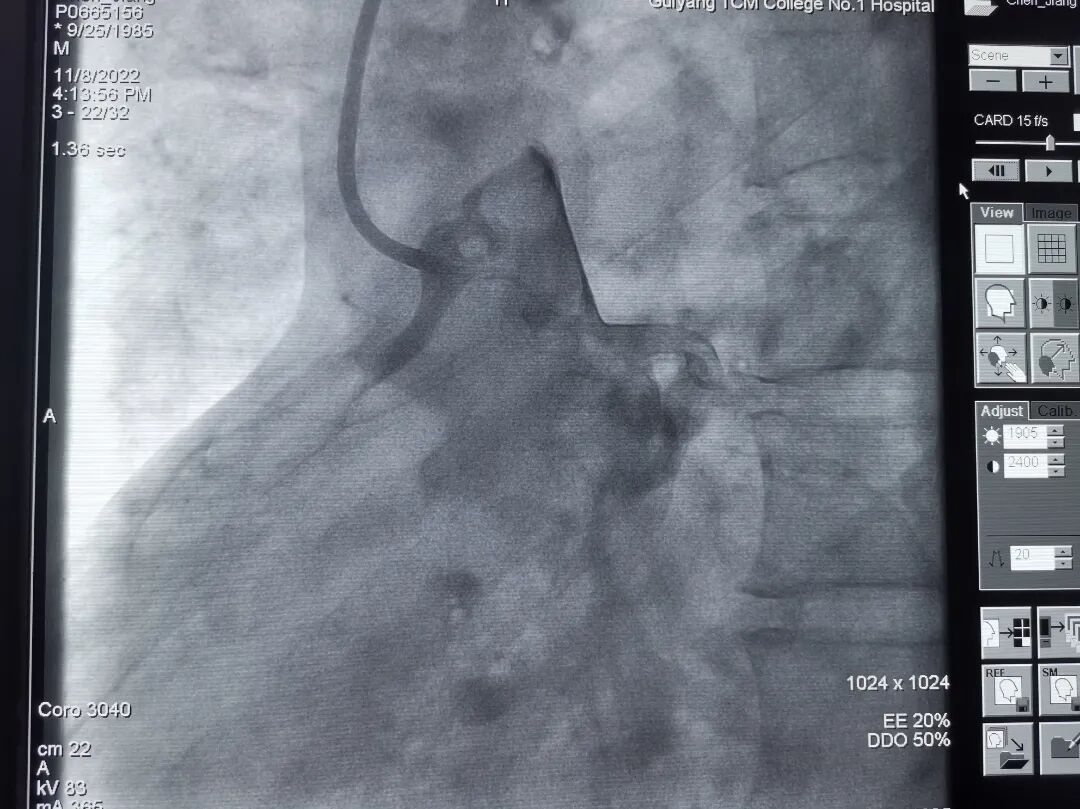

118日,在介入室的配合下,由郑涛副主任医师主刀,郭英普主治医师和封挺约主治医师为助手,为患者开展冠脉介入手术。术中选择了右侧股动脉路径,尝试多次后JR造影管终于找到右冠脉开口,造影显示右冠开口在升主动脉后壁并高于左冠开口,为极少见的冠脉变异开口,同时造影显示右冠近段以远完全闭塞,前向血流TIMI 0级。

造影导丝是什么再克技术堡垒  巧破闭塞病变——心血管内科应用平行导丝技术救治冠脉慢性完全闭塞患者!_https://www.jmylbn.com_新闻资讯_第5张

右冠脉造影显示右冠开口变异伴右冠完全闭塞